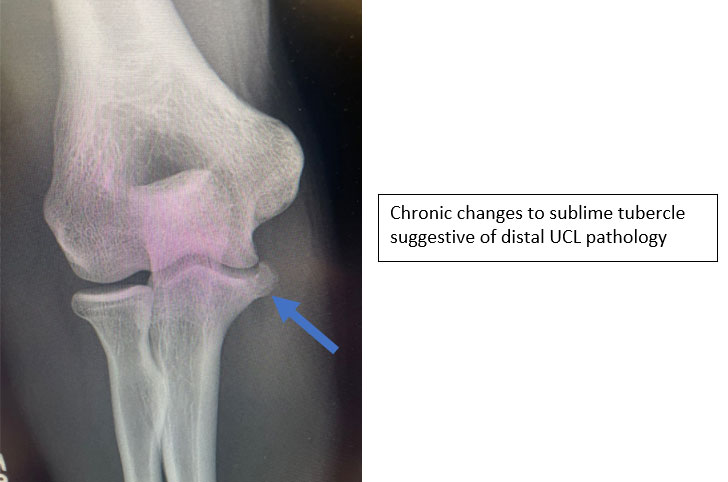

- An athlete with a suspected UCL injury will undergo initial X-rays to look for any loose bodies, stress fractures, bone spurs or even avulsion fractures

- Full thickness tears, distal tears, partial tears with significant edema or chronic ligamentous changes have been shown to have less healing potential

Proximal Ulnar Collateral Ligament reconstruction with chronic calcified ligamentous changes and bony fragments not amenable to repair and therefore requiring reconstruction